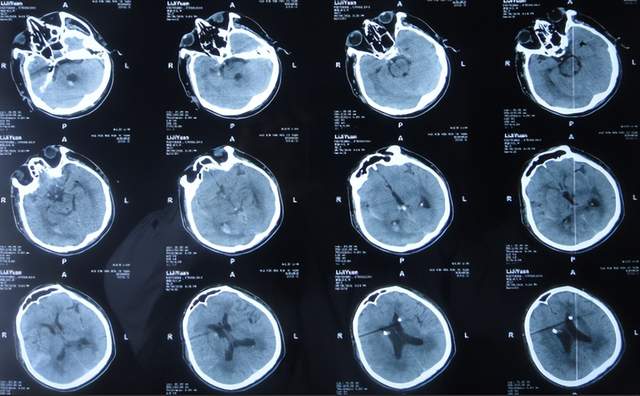

2022年4月7日(入院治疗50天),查头颅CT示脑室引流术后状态,未见异常(图-22)。

图-22:2022年4月7日头颅CT

2022年4月27日(入院治疗70天)家属要求出院回家休养。出院时:携带脑室腹壁外引流管;精神变得挺好,能自己站立但自己走路不稳,体重较入院时明显增加,入院时消瘦病态的体型已基本恢复正常状态(图-23);出院时头颅CT示脑室引流状态(图-24)。

图-24:出院时头颅CT

出院后4个月即2022年8月30日,为了做脑积水分流术,再次来到李小勇脑脊液科,入院时:精神状态良好,能自己走路了稍不稳(图-25);头颅CT示脑室引流术术后状态(图-26)。

图-26:2022年8月30日头颅CT

完善各项检查后于2022年9月15日,进行了脑室腹腔分流术(图-27)。

图-27:2022年9月15日头颅CT

脑室腹腔分流术后13天即2022年9月28日出院。出院时:走路进一步变稳,身体其他均正常(图-28)。